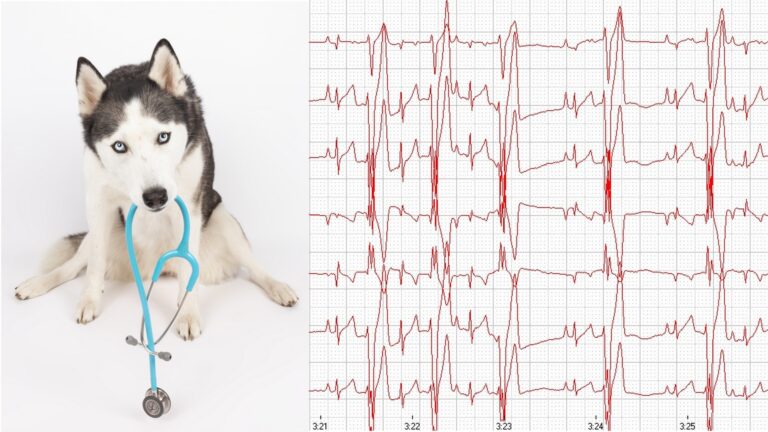

Um eine Herzerkrankung korrekt zu diagnostizieren reicht es nicht, ein Tier abzuhören. Das Vorliegen eines Herzgeräuschs oder einer Rhythmus-Veränderung ist nicht beweisend für eine Herzerkrankung. Beim Verdacht auf eine Herzerkrankung müssen mindestens ein Herzultraschall und ein EKG durchgeführt werden. Beides ist am wachen Patienten möglich und für das Tier nicht belastend. Nur mithilfe dieser Untersuchungsmethoden kann eine klare Diagnose gestellt werden. Diese ist nötig, um eine zu planen. Es gibt weitreichende Therapieoptionen, die von Medikamenten über Fütterungs- und Management-Maßnahmen bis hin zu Operationen reichen. Wichtig ist außerdem, Begleiterkrankungen oder andere Grundursachen zu finden.